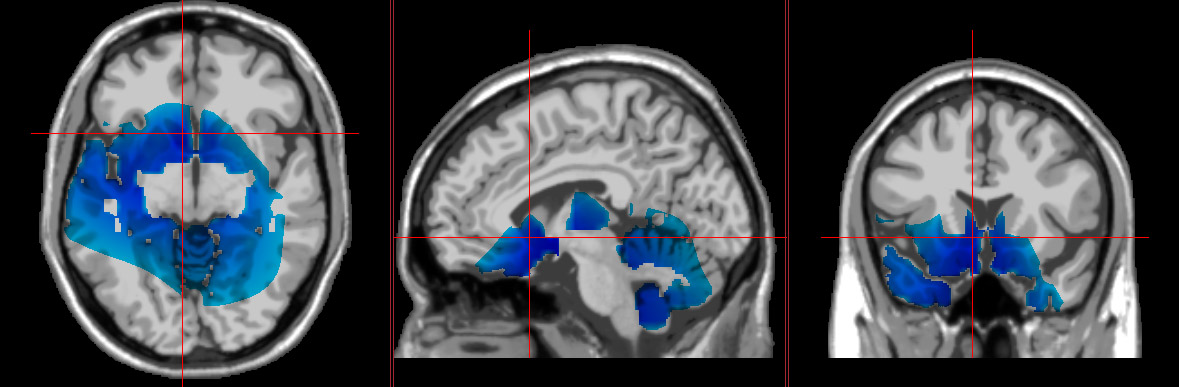

blue areas of brain represent depression from QEEG EEG scan showing signs of depression loreta neurofeedback showing the brain with depression what having depression looks like in your brain with loreta neurofeedback